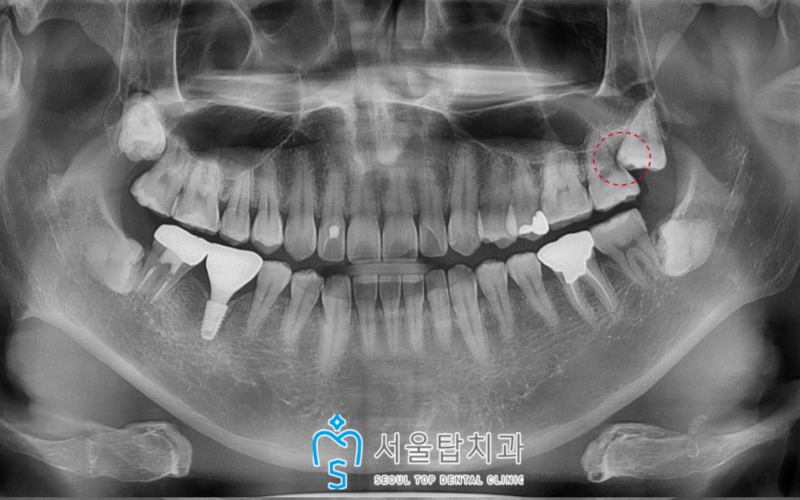

위 사진은 발치 후 한달쯤 지나서

찍은 사진이랍니다.